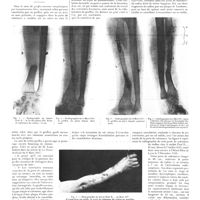

0012 - Page 8 - Sociétés de Paris. Académie de médecine. 2 janvier 1916 / Analyses. Syphiligraphie. Nicolau... Un cas d'infection syphilitique cryptogénétique (Annales de dermatologie et syphiligraphie, t. VI, n° 4, 1916, juillet, p. 186-198) / Chirurgie pratique. Entorse et examen radiologique [L. Delherm et G. Boileau]0012 - Page 8 - Sociétés de Paris. Académie de médecine. 2 janvier 1916 / Analyses. Syphiligraphie. Nicolau... Un cas d'infection syphilitique cryptogénétique (Annales de dermatologie et syphiligraphie, t. VI, n° 4, 1916, juillet, p. 186-198) / Chirurgie pratique. Entorse et examen radiologique [L. Delherm et G. Boileau]